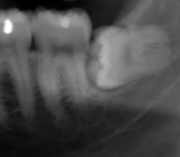

For partially impacted teeth in those over 20 year of age, the most common pathology seen, and the most common reason for wisdom teeth removal, is pericoronitis or infection of the gum tissue over the impacted tooth. The bacteria associated with infections include Peptostreptococcus, Fusobacterium, and Bacteroides bacteria. The next most common pathology seen is cavities or tooth decay. Fifteen percent of people with retained wisdom teeth exposed to the mouth have cavities on the wisdom tooth or adjacent second molar due to a wisdom tooth. The rate of cavities on the back of the second molar has been reported anywhere from 1% to 19% with the wide variation attributed to increased age.[10]

In five percent of cases, advanced periodontitis or gum inflammation between the second and third molars precipitates the removal of wisdom teeth.[3]:141[4] Among patients with retained, asymptomatic wisdom teeth, roughly 25% have gum infections (periodontal disease).[11]:ch13 Teeth with periodontal pockets of greater than 5mm have tooth loss rates that start at 10 teeth lost per 1000 teeth per year at 5mm to a rate of 70 teeth lost per year per 1000 teeth at 11mm.[12]:57 The risk of periodontal disease and caries on third molars increases with age with a small minority (less than 2%) of adults age 65 years or older maintaining the teeth without caries or periodontal disease and 13% maintaining unimpacted wisdom teeth without caries or periodontal disease.[13] Periodontal probing depths increase over time to greater than 4 mm in a significant proportion of young adults with retained impacted wisdom teeth which is associated with increases in serum inflammatory markers such as interleukin-6, soluble intracellular adhesion molecule-1 and C-reactive protein.[14]